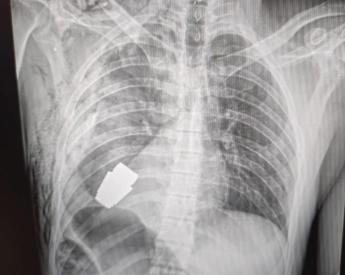

Granata nel torace del soldato, l’operazione in Ucraina

(Adnkronos) – Un’operazione per estrarre una granata non esplosa dal corpo di un soldato dell’Ucraina. Anton Gerashenko, consulente del ministero dell’Interno di Kiev, sui social pubblica la foto che documenta l’intervento eseguito dal chirurgo militare Andrii Verba. L’operazione, per estrarre la granata dal torace del militare, è stata effettuata alla presenza di due militari del […]